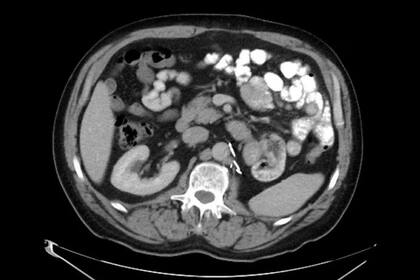

MADRID.— El tratamiento habitual para las personas con cáncer de riñón avanzado es la cirugía para extirpar el tumor. Después, se aplica inmunoterapia, un tipo de tratamiento que ayuda al sistema inmune a atacar el cáncer, para reducir el riesgo de recaída. Con esta combinación terapéutica, un tercio se recuperan, pero el resto sufren recidivas y se quedan con pocas opciones.

Hoy, la revista Nature publica los hallazgos de un estudio piloto realizado con nueve pacientes con cáncer renal. En él, investigadores del Instituto del Cáncer Dana-Farber de Boston (EE. UU.) y otras instituciones estadounidenses, administraron una vacuna personalizada tras la cirugía con el objetivo de estimular una respuesta inmunitaria capaz de eliminar cualquier célula tumoral remanente y prevenir una posible recaída. A cinco de ellos, también les dieron ipilimumab, un medicamento inmunoterápico. Después de tres años de seguimiento, todos los pacientes seguían libres de cáncer.